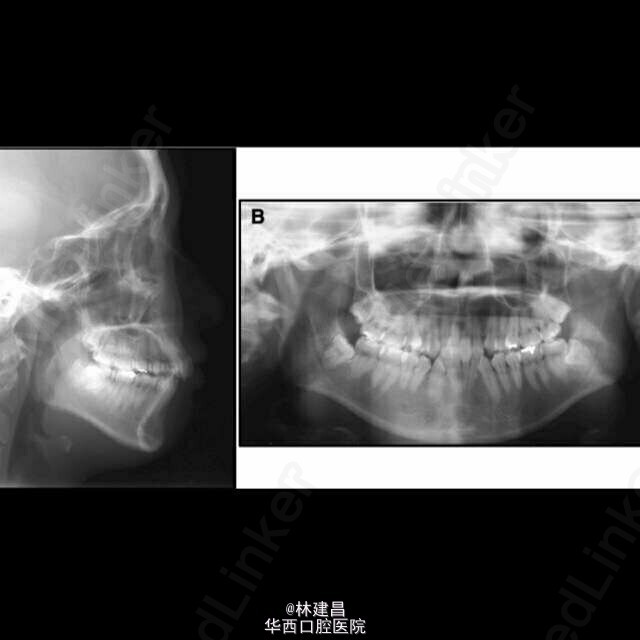

舌侧矫治技术联合舌弓治疗复杂安氏II类2分类一例

舌侧矫治技术中因为视野有限、托槽之间距离短、弓形不规则和复杂的粘结/去粘结等因素,让舌侧矫治的推广收到一定限制,曾出现了一段时间的停滞发展。随着舌侧自锁托槽等一系列新技术的出现(包括直丝弓技术、个性化定制托槽、弓丝弯制机械手、种植钉支抗技术等)让舌侧矫治技术得到进一步完善,目前在临床上又出现了再度复兴之势。但有临床医师提出仍然有一个问题舌侧矫治尚难以解决,即在复杂病例中,舌侧矫治器无法和舌侧辅助装置联用。例如在有横向不调的患者中,舌侧矫治器无法与舌弓、四眼圈簧、固定式快速扩弓装置联用。因此用舌侧矫治技术治疗有多个维度上不调的复杂正畸病人存在一定困难。如下为大家介绍了一例用舌侧矫治技术治疗安氏II类患者伴上颌弓狭窄、第二磨牙反合的病案。因患者不同意做正颌手术,且因美观需求强烈要求行舌侧矫治。若使用常规舌侧矫治技术,患者严重的水平向和垂直向不调将难以解决,所以该病例主诊医师改良了舌侧矫治技术,配合舌弓的应用,治疗结果证明,该方法有效。